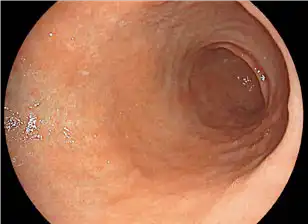

The newly designed high performance optical system enhances close focus observation capability up to 2 mm.

The focus at the edges of an image has been improved,minimizing distortion in observation of a lumen. Through a combination with the megapixel CMOS image sensor, high performance optical system assists various observations ranging from close-up to distant views.